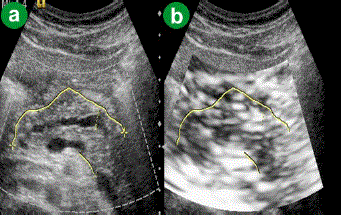

Figure 3. Chronic pancreatitis. a. US B-mode image. b. eSie touch gray scale image (light gray to gray: score 2-3).